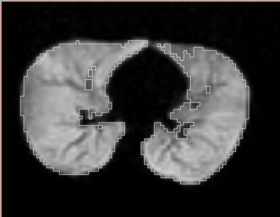

* Correction of the bias in vervet MRI. Acquisition parameters: 3T GE scanner, single-channel dedicated RF coil (Litzcage, Doty Scientific, Columbia, SC); 3D SPGR sequence (TI 600ms, TE 3.276ms, TR 15.28ms; flip angle 15 deg; matrix 256x256; FOV 12cm; in-plane resolution 0.47 mm; slice thickness 0.5 mm). | * Correction of the bias in vervet MRI. Acquisition parameters: 3T GE scanner, single-channel dedicated RF coil (Litzcage, Doty Scientific, Columbia, SC); 3D SPGR sequence (TI 600ms, TE 3.276ms, TR 15.28ms; flip angle 15 deg; matrix 256x256; FOV 12cm; in-plane resolution 0.47 mm; slice thickness 0.5 mm). | ||

- Correction of the bias in vervet MRI. Acquisition parameters: 3T GE scanner, single-channel dedicated RF coil (Litzcage, Doty Scientific, Columbia, SC); 3D SPGR sequence (TI 600ms, TE 3.276ms, TR 15.28ms; flip angle 15 deg; matrix 256x256; FOV 12cm; in-plane resolution 0.47 mm; slice thickness 0.5 mm).